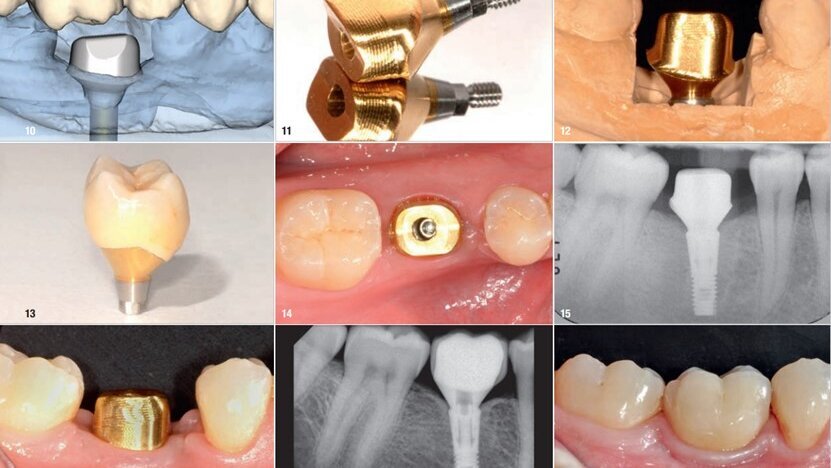

图10:根据被替换磨牙的实际露出宽度设计Atlantis基台,用钛制造,外层涂有氮化钛涂层。

图11:Atlantis镀金钛合金基台和配套螺丝钉一起被送往牙科实验室。

图12:基台的龈下部分将为周围软组织提供解剖外形、支持和色泽。最后的修复冠由氧化锆制作。

图13:最终种植修复的修整线应接近牙龈边缘,以便于去除龈下区域多余的水门汀。修复体已准备好交给病人。

图14:Atlantis基台置于软组织上并稍加压,几分钟后缺血恢复,基台正确就位。

图15:使用X线机器检验基台是否正确就位。注意基台的过渡部分应遵循骨轮廓。

图16:根据制造商建议,将镀金钛合金Atlantis基台以25Ncm扭矩拧紧。螺丝钉头被覆盖,之后牙冠用水门汀粘于基台上。

图17:十年后X线显示修复体、为邻面乳头创造的空间和种植体水平的骨量非常合适。

图18:十年后观察到修复体周围软组织适应良好(颊面视图),邻面乳头填充了预留空间,形成自然的软组织轮廓。